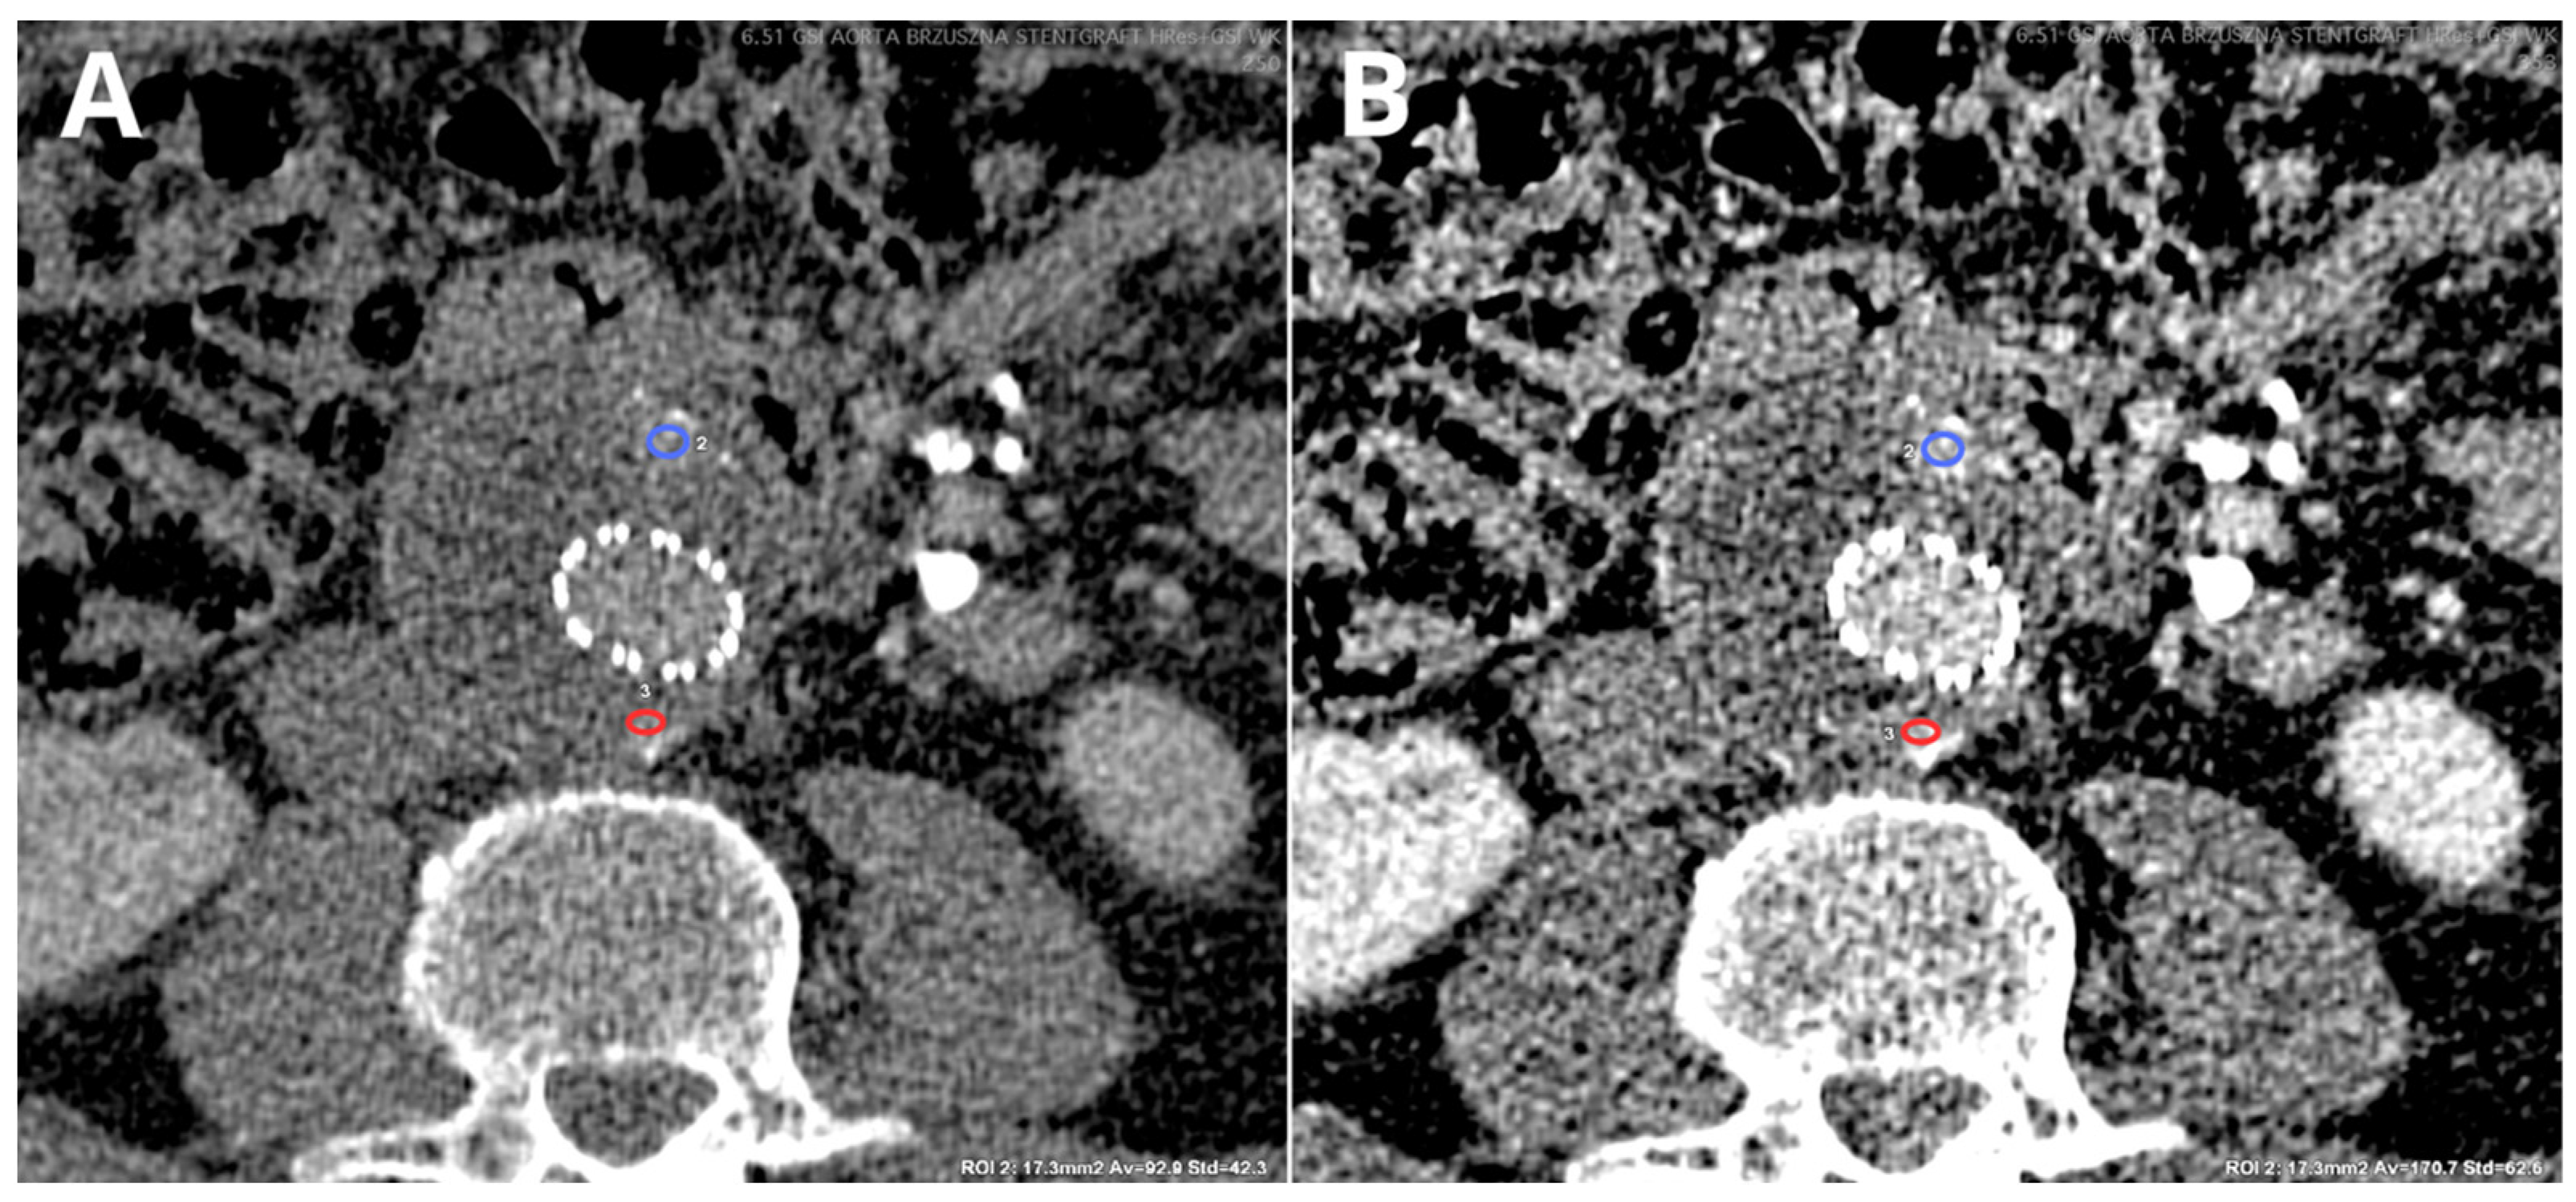

- Kazimierczak, W.; Kazimierczak, N.; Serafin, Z. Quality of Virtual-Non-Contrast Phases Derived from Arterial and Delayed Phases of Fast-KVp Switching Dual-Energy CT in Patients after Endovascular Aortic Repair. Int. J. Cardiovasc. Imaging 2023, 39, 1805–1813. [Google Scholar] [CrossRef] [PubMed]